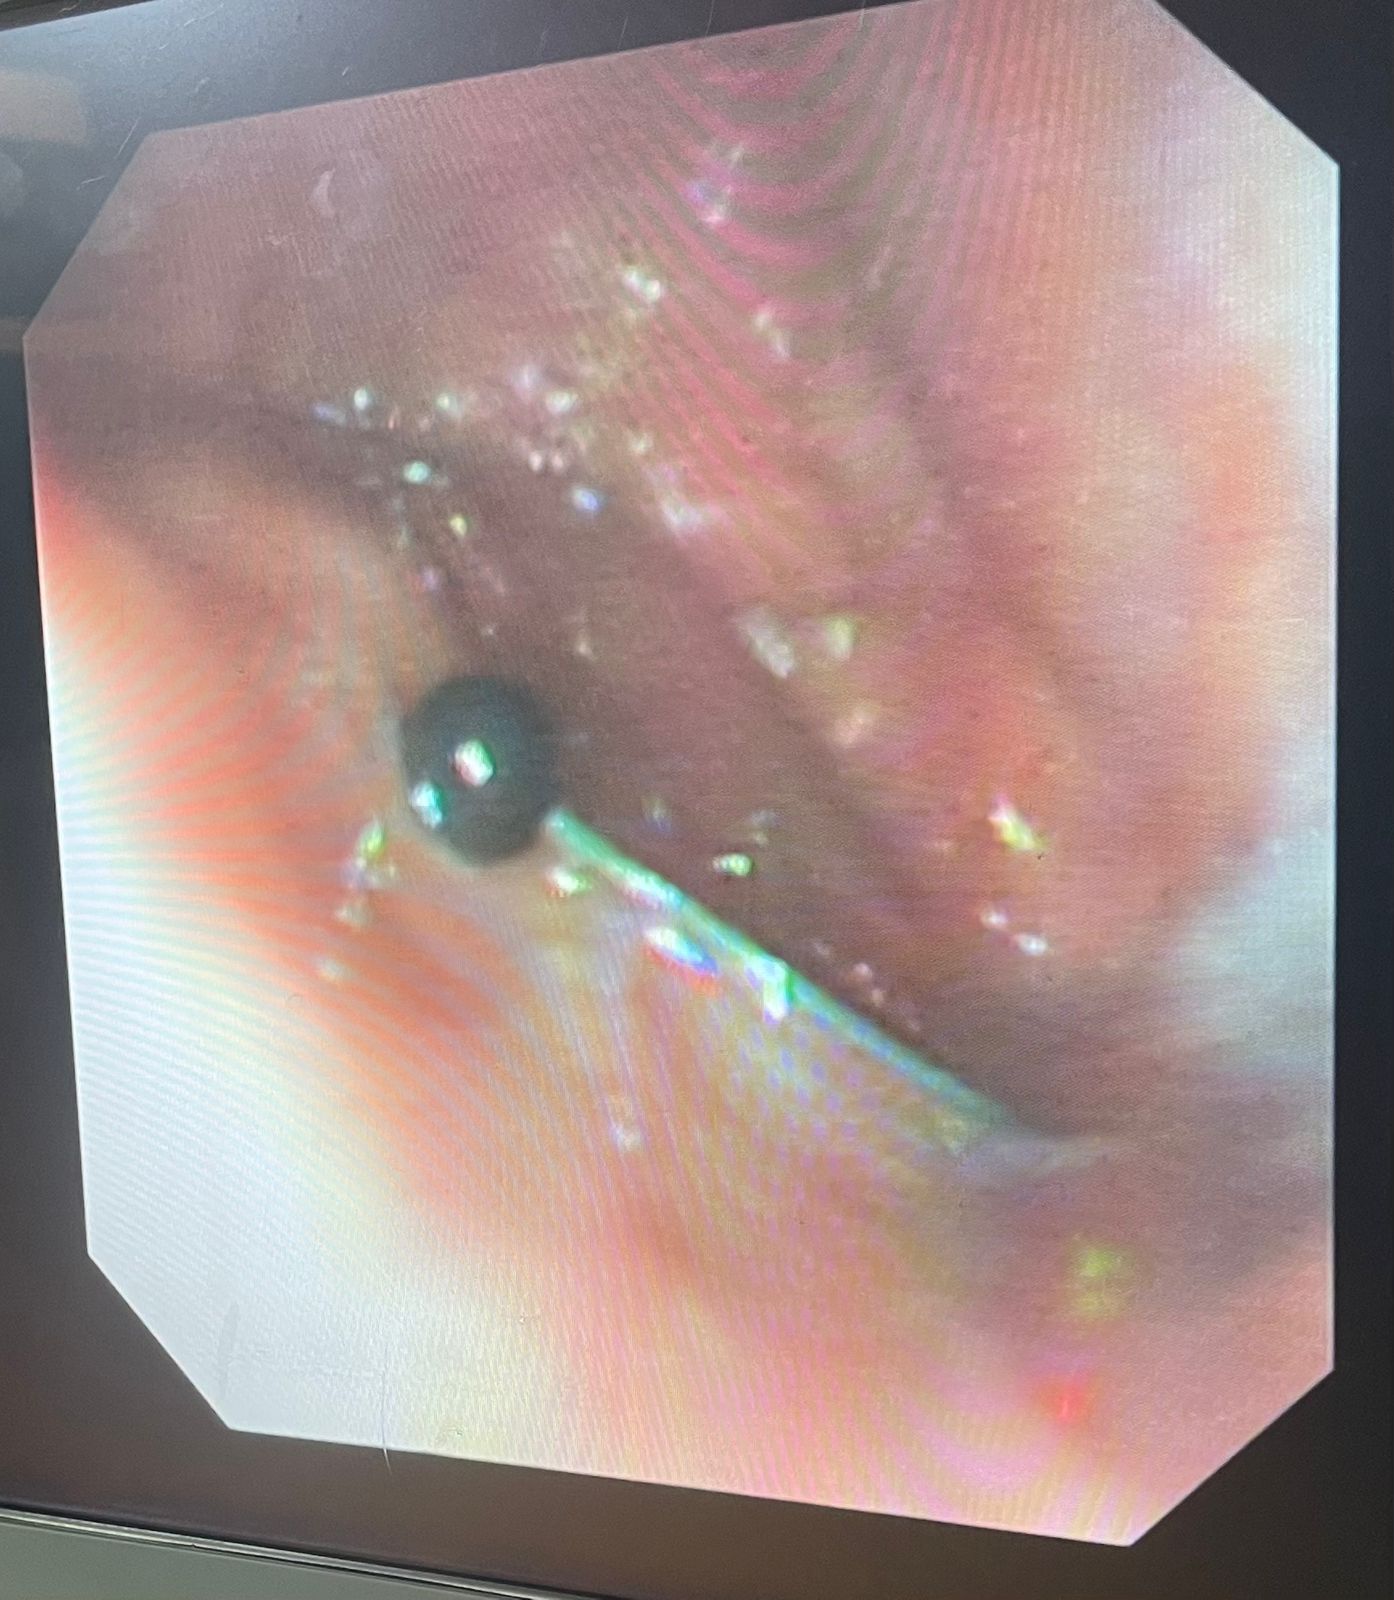

نجح فريق طبي من وحدة أمراض الجهاز الهضمي والكبد ومناظير الأطفال بقسم طب الأطفال بـ مستشفى سوهاج الجامعي في إجراء تدخل دقيق لاستخراج دبوس من معدة طفل عمره 4 سنوات، بإستخدام منظار معدة خاص بالأطفال، دون حدوث أي مضاعفات، وقد غادر الطفل المستشفى بعد ثلاث ساعات فقط من الإجراء، وهو في حالة صحية جيدة.

وأكد الدكتور أحمد كمال، المدير التنفيذي للمستشفيات الجامعية، أن التعامل مع الحالة تم بسرعة وكفاءة، حيث تمكن الفريق الطبي بـ مستشفى سوهاج الجامعي من استخدام المنظار الخاص بالأطفال لاستخراج الدبوس دون أي تدخل جراحي، مما ساهم في خروج الطفل من المستشفى في نفس اليوم بحالة ممتازة.